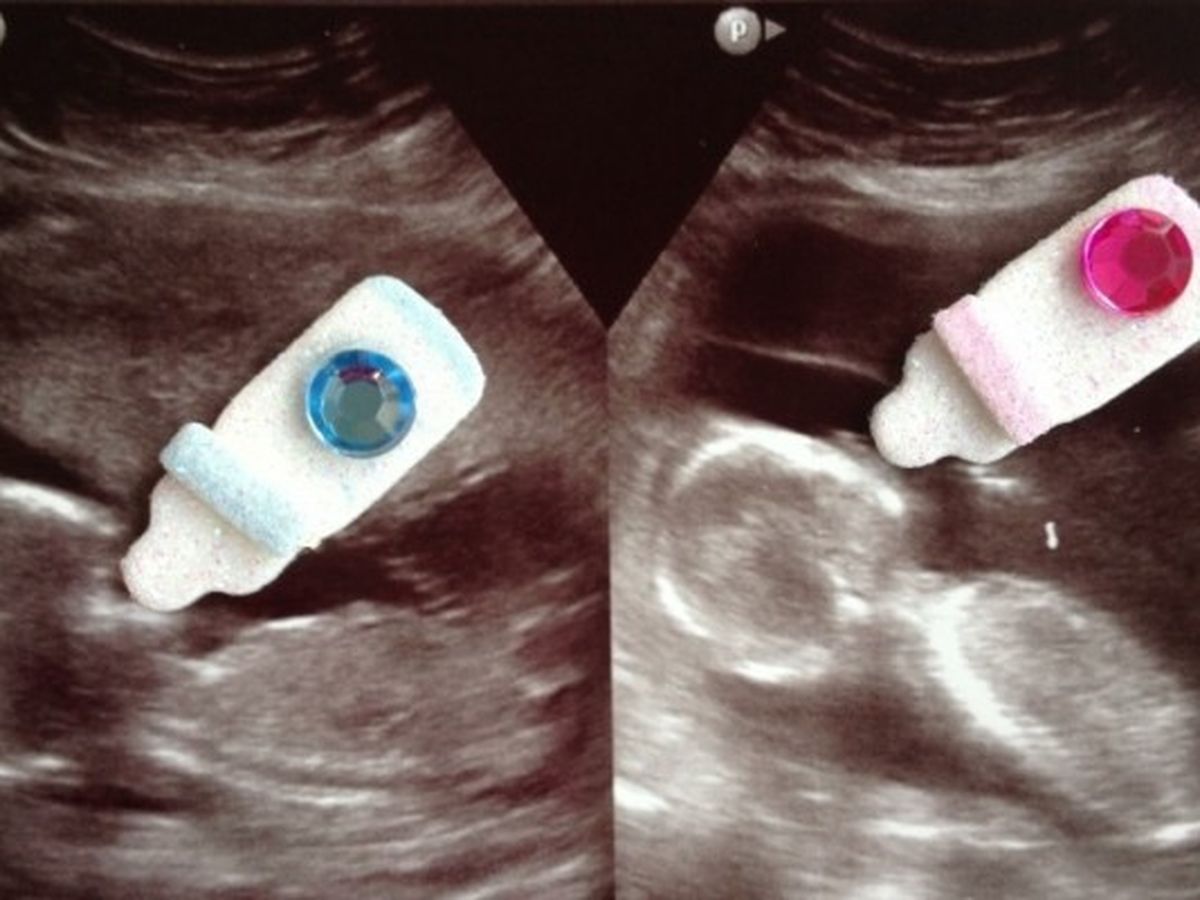

I am posting this story to help my brother in law, Delbert Perkins and his wife, Stephanie Perkins. They are expecting twins.

At 28 weeks they found out that the baby boy, Jessie Kole has a small hole between ventricles of his heart which will probably close on its own. Baby Girl, Annalise Claire has some severe cardiac problems, but they will be fixed with open heart surgery at birth. She will also be born with Down Syndrome.